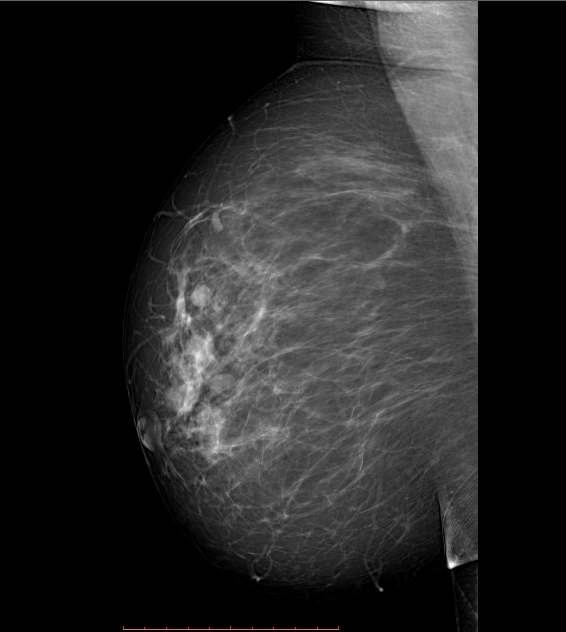

Phân loại Bi-RADS

Phân loại BI-RADS (Breast Imaging Reporting and Data System- BI-RADS)